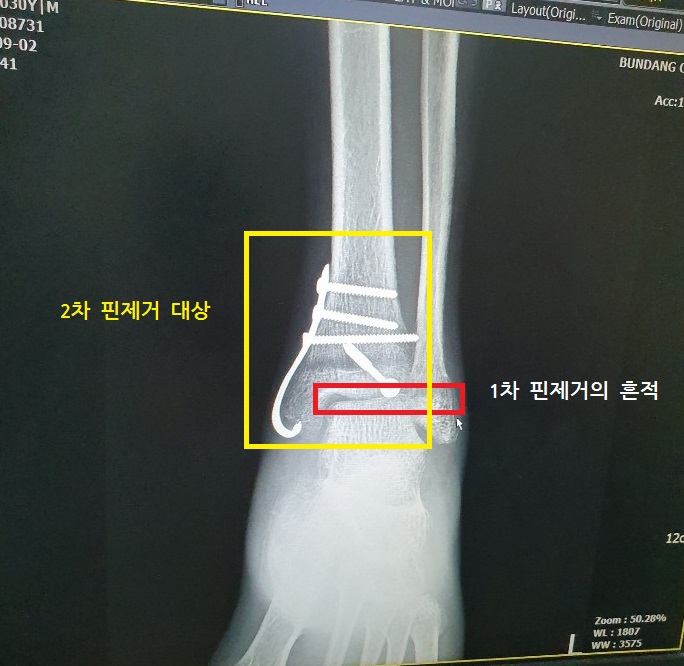

사진에 표시를 잘못했는데,

1차 핀제거는 조금 더 위쪽 검은 라인이다. 하핫;

9월 2일 병원에 갔으니,

골절 14주차, 수술한지 12주차, 1차 핀제거 한지 2주차.

2차 핀제거 수술

핀제거 수술은 사실 선택이다.

하지만, 제거를 권한다.

특히 앞으로 움직일 날이 많다면 더더욱!

뼈가 핀 위로 덮혀서 자라게 될 수 있다고 한다.

그렇게되면 뼈 모양도 이상해질 것이고,

뒤늦게 제거하려들면 그 뼈를 다시 날려야하기 때문에 난이도도 올라간다.